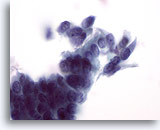

Adenocarcinoma in situ

Endocervical cells presenting in a pseudo-rosette formation and exhibiting “feathering” and nuclear elongation due to crowding. Biopsy – AIS – 60x